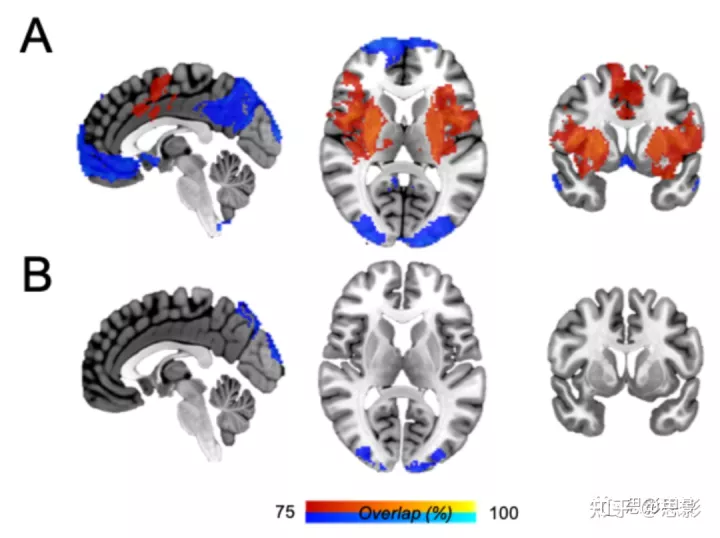

图 S4:病变网络重叠结果。

个体病变网络被阈值化、二值化,然后覆盖成瘾缓解(A)和不戒烟(B)相关的病变。体素值表示在功能上连接到该体素的病变位置的数量(以阈值 75% 的病变位置显示)。与未戒烟患者的病变相比,与成瘾缓解相关的病变的病变网络重叠要高得多。